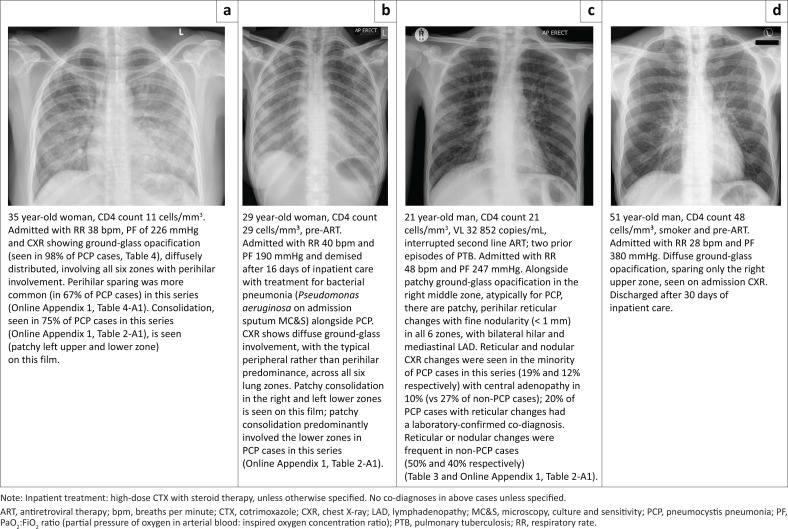

Results: Records from 104 adults (52 PCP cases and 52 non-PCP controls) were included. Diffuse versus patchy ground-glass opacification was associated with increased odds of PCP diagnosis (adjusted odds ratio [aOR]: 6.2, 95% confidence interval [CI]: 1.6-28.9, P = 0.01) and severe PCP (aOR: 4.5, 95% CI: 1.6-14.4, P = 0.008). Consolidation was associated with severe PCP (aOR: 3.3, 95% CI: 1.2-11.0, P = 0.03) as was increasing ground-glass zone involvement (aOR: 2.1 for each one-unit increase in involved zone; 95% CI: 1.4-3.2, P = 0.0004). Models incorporating hypoxia (hypoxia model) or tachypnoea (respiratory rate model) with diffuse ground-glass opacities, absence of pleural effusion or reticular/reticulonodular changes on CXR performed well in predicting PCP (area under the receiver operating characteristic curve 0.828 [hypoxia model] and 0.857 [respiratory rate model]).

Conclusion: CXR evaluation alongside bedside clinical information offers good accuracy for discriminating definite PCP from other HIV-associated respiratory diseases.